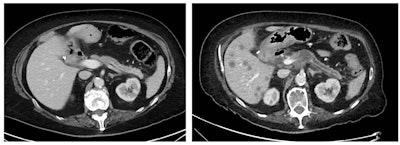

Abdominal and pelvic CT and MRI scans were independently reviewed by radiologists to develop an algorithm to categorize the missed cases and identify the most likely explanation for why they were missed.

The researchers found that in 10% of PIPC patients, imaging signs associated with pancreatic cancer, such as dilated bile or pancreatic ducts, were not recognized as such and not investigated further.

In the previous scans of 13 patients (26%), the signs of a mass lesion were not picked up by the radiologist, Umar added.

"The identification rate of pancreatic cancers are dictated by the size of the lesion and the amount of isoattenuating small tumors," explained Marti-Bonmati, who was made a gold medallist of the European Society of Gastrointestinal and Abdominal Radiology in 2018. "The imaging technique is critical to the success in identification of pancreatic cancers."

In CT, the dose concentration and rate of contrast administration are vitally important to identify pancreatic tumors, and the use of spectral CT or dual-energy CT scanners can help to pick up isoattenuating tumors at low or standard energy, he pointed out. For further reading in this area, Marti-Bonmati recommends the recent "Insights into Imaging" article by Dr. Hongwei Liang and colleagues.

There is always a certain rate of missed cancers, sometimes because of underlying confounding factors, such as chronic pancreatitis mimicking or masking a mass, noted Dr. Rossano Girometti, associate professor of radiology at Udine University Hospital in Italy. "It can be a difficult diagnosis, even for the pathologist," he said.

He added that a pancreatic lesion may be missed because the case is inherently difficult, such as isodense cancers or cancers arising in a chronic pancreatitis context, and this can happen because of the nature of the lesion or pancreatic background.